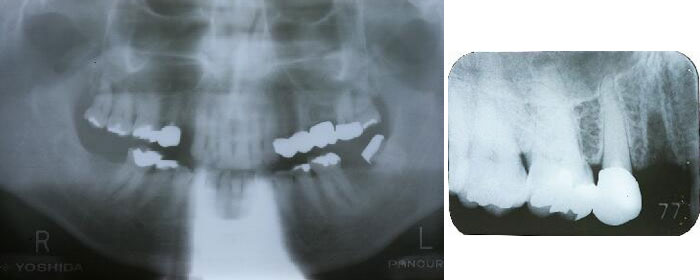

症例3 抜歯と同時に埋入した症例 年齢63歳 男性

初診時の状況

・右上4番の痛み(下の大きなエックス線写真では左の上の歯を抜いたところです)

・歯根歯折があり抜歯と決定

・前後の歯を削りブリッジタイプのかぶせ物を検討したが、健康な歯を切削するのは希望しない

との事でインプラントを選択

抜歯直後のエックス線写真

抜歯した後の窩洞より太いインプラント体(フィクスチャー)を用意